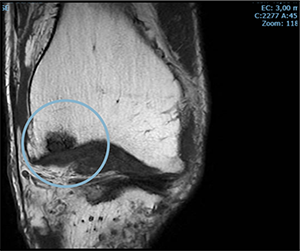

PRE TREATMENT

November 2023

POST TREATMENT

November 2024